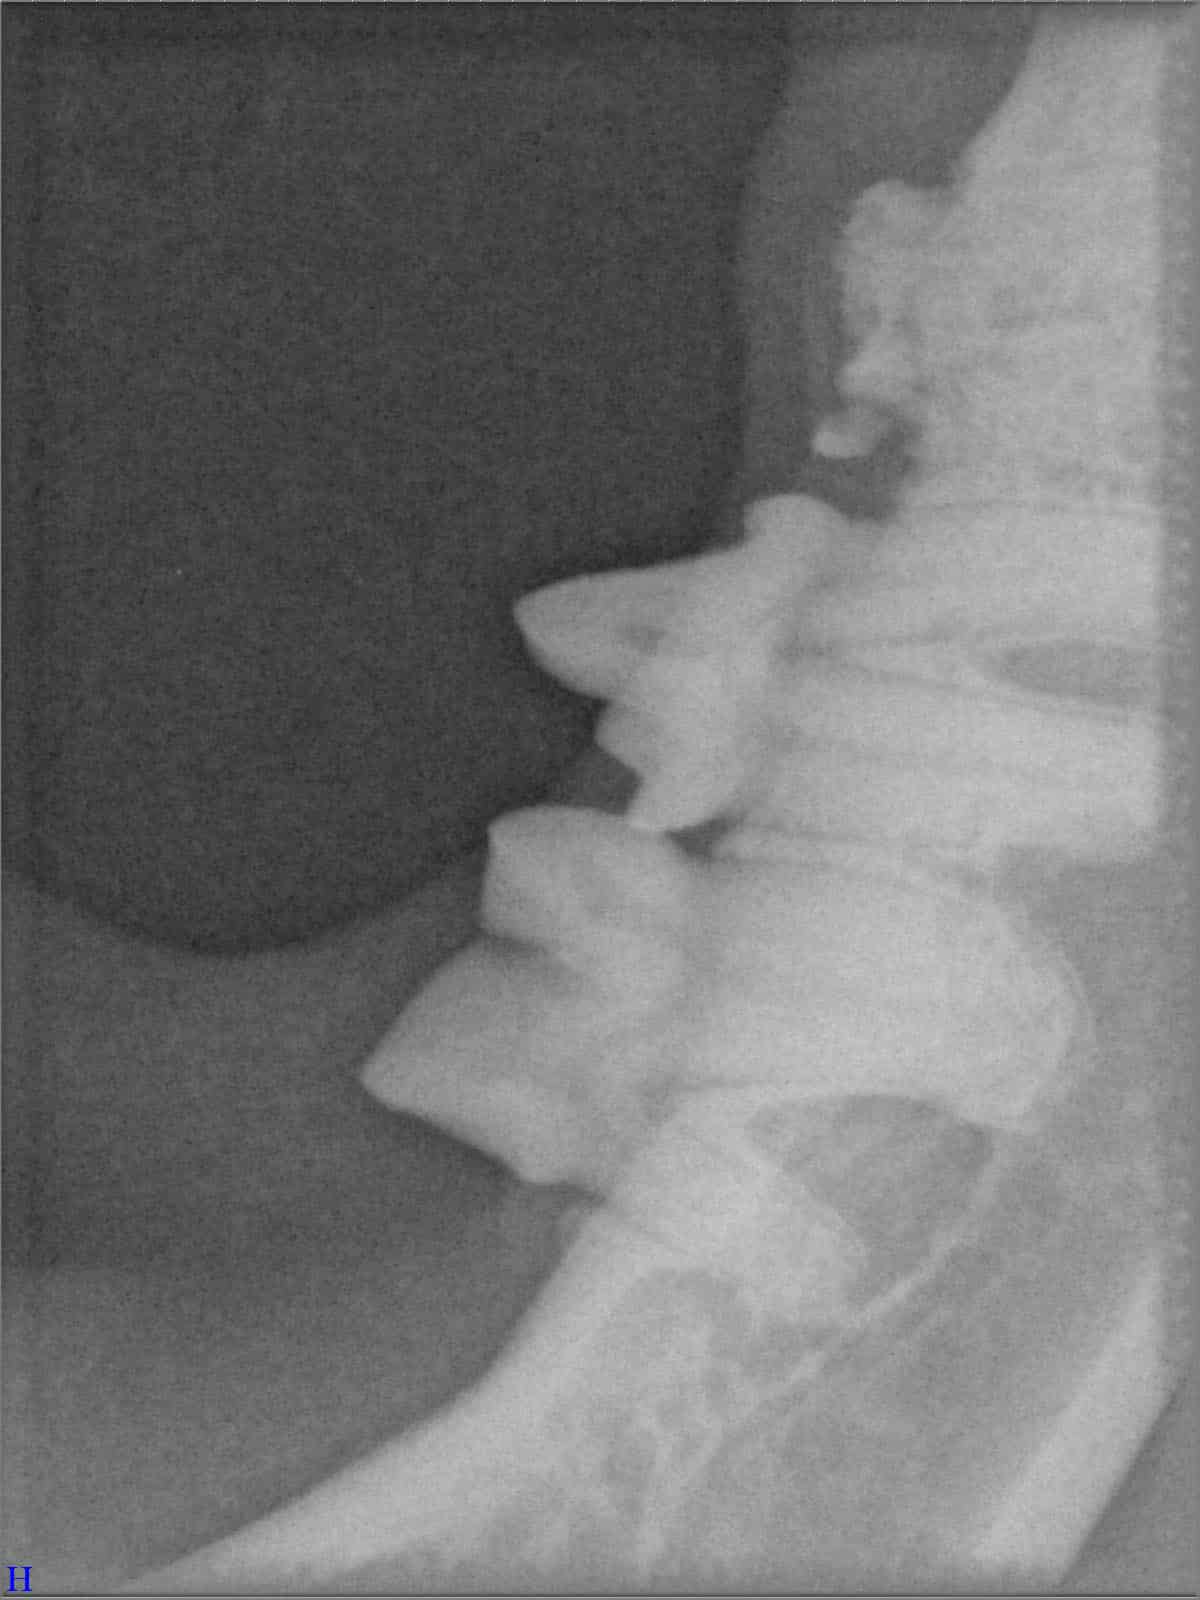

Das sehen Sie von außen – so sieht es auf den Röntgenbildern aus.

FORL Katze Röntgenbild

Röntgenbilder